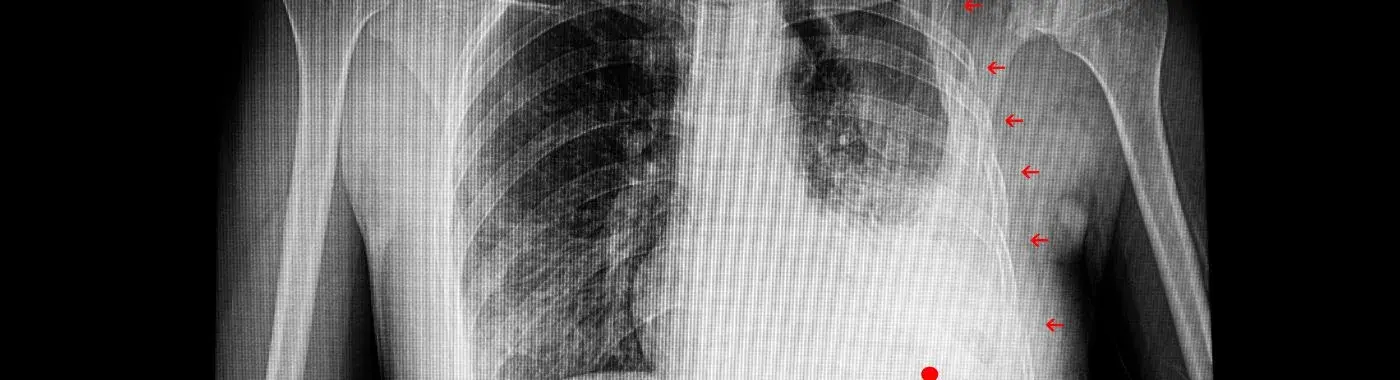

• Imaging Studies: Chest X-rays are commonly used to visualize rib fractures and assess lung function. CT scans may be ordered for a more detailed view of the chest structures.